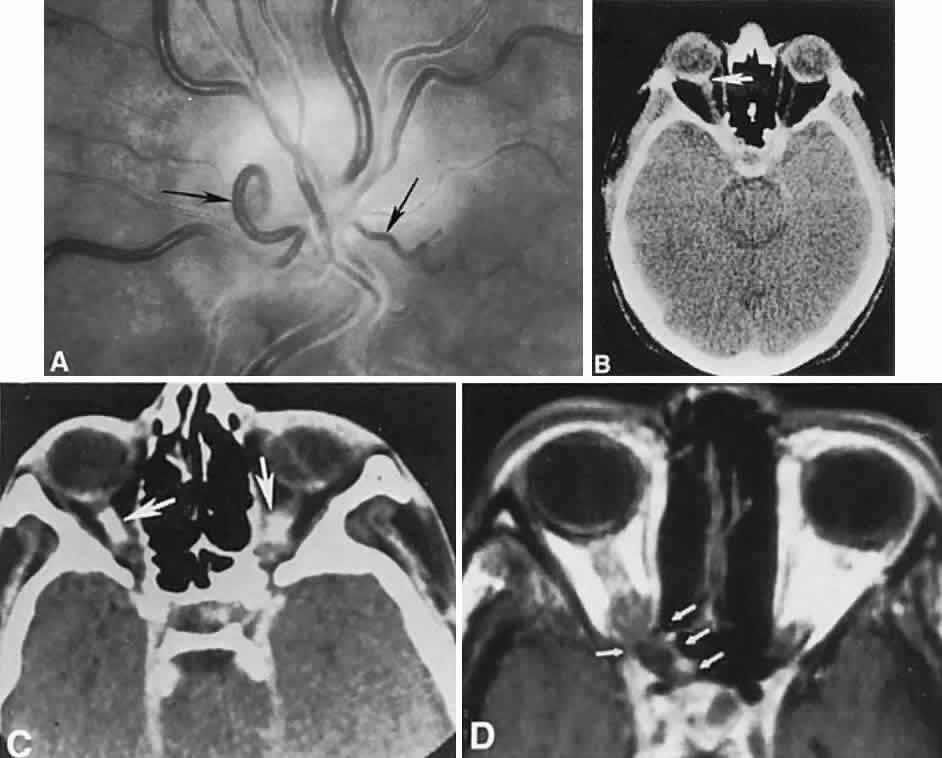

CONGENITAL HAMARTOMA SYNDROMES

The “neurophakomatoses” are a diverse group of disorders nosologically related by the presence of hamartomatous lesions, and, indeed, the term “hereditary hamartomatosis” is a more accurate description. However, whereas neurofibromatosis, tuberous sclerosis, and von Hippel-Lindau disease are transmitted with irregular dominance and considerable variation in penetrance, no hereditary basis of Sturge-Weber or angio-osteohypertrophy (Klippel-Trenaunay-Weber) syndrome has been established.

A hamartoma is a tumor of anomalous origin composed of elements normally present in the tissue in which it originates and with a limited capacity for proliferation. The following tumors may be classified as hamartomas: (1) in neurofibromatosis: optic gliomas (see Chapter 6), neurofibromas, and ganglioneuromas; (2) in tuberous sclerosis: retinal and cerebral astrocytomas, cutaneous angiofibromas (“adenoma sebaceum”), rhabdomyomas, and leiomyomas; (3) in von Hippel-Lindau disease: hemangioblastomas of the cerebellum and retina (including optic nerve head) and renal hypernephromas or cysts; (4) in Sturge-Weber disease: facial and choroidal cavernous hemangiomas and meningeal angiomatous malformations; and (5) in Klippel-Trenaunay-Weber syndrome: cutaneous nevi, visceral and limb hemangiomas, and orbitofacial venous varices.

If all disorders with neurocutaneous manifestations are considered, the term phakomatoses (Greek, phakos, “spot,” “birthmark”) is appropriate, and the catalog of “related” disorders becomes cumbersome. “The Phakomatoses,” Volume 14 of Vinken and Bruyn's Handbook of Clinical Neurology, is extraordinarily complete and serves as a source of detailed clinical descriptions of these diseases.146 Syndromes characterized by vascular hamartomas, that is, retinal-cerebellar angiomatosis (von Hippel-Lindau), and other angiomatous malformations, are discussed in Volume 2, Chapter 17.